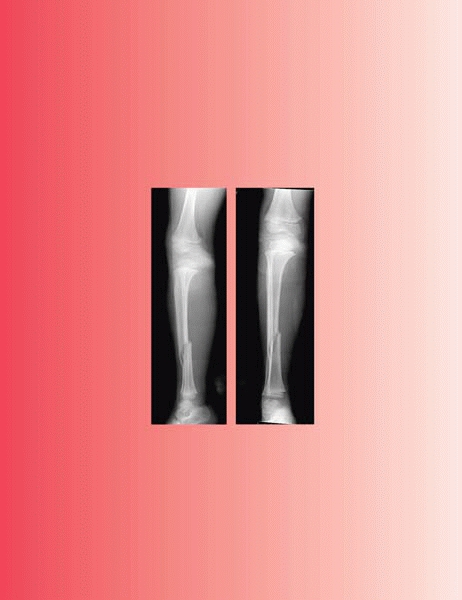

▪ FIGURE 9-13 A,B:

A spiral fracture of the tibia may be difficult to appreciate if only one radiographic view is obtained. These radiographs illustrate the importance of orthogonal radiographs when evaluating a child with the possibility of a fracture. |